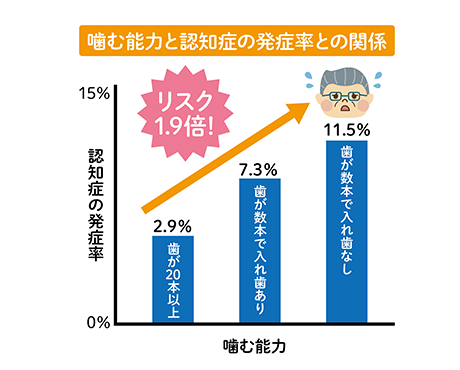

「認知症」とは、認知機能が低下し日常生活に支障を与える脳の病気です。

歯を失った後、入れ歯などを使わずにそのままにしている方は認知症の発症リスクが高いことが分かっています。

歯を失ったからとそのまま放置せず、入れ歯を使用して噛み合わせを維持することが重要です。

よく噛むことによって、 脳の神経が刺激され活発になります。

これにより記憶力や集中力も増します。